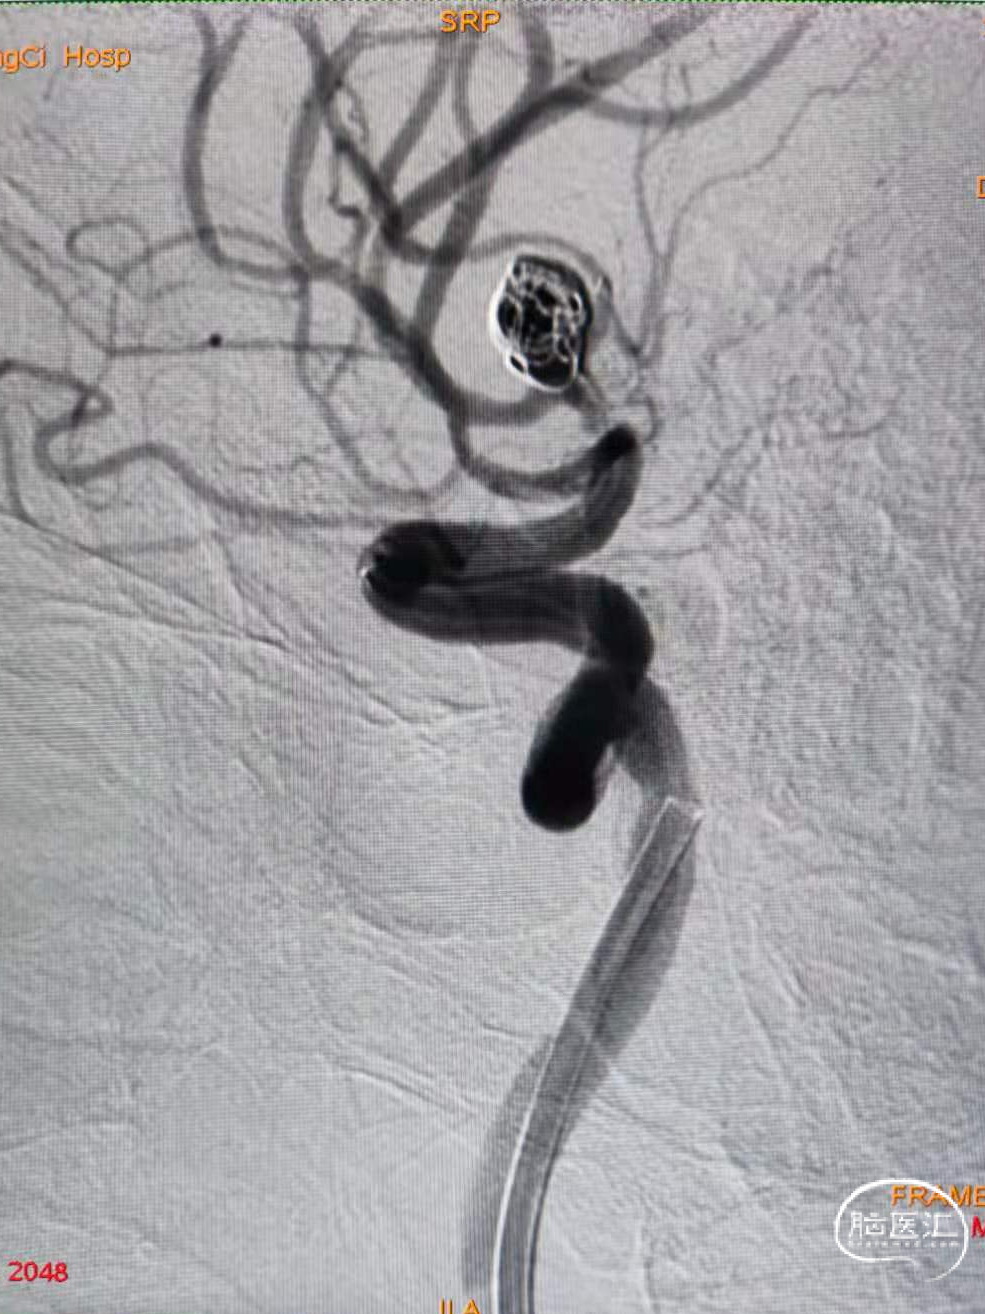

脑血管造影显示右侧大脑中动脉分叉部宽颈动脉瘤,约7.4-7.0-6mm大小。动脉瘤为不规则形态,右侧中动脉上下支干均受累,其中上支干纤细约1.0mm,自瘤体近瘤颈处发出。

术前影像

1、与术前分析的一致,由于上支干与M1成角以及瘤颈很宽等因素,微导管超选上支干很困难。最终选择微导丝及微导管瘤体内成袢进入上支干很远后再缓慢逐步回撤微导管解袢。(该步骤风险很大,因为动脉瘤破裂点在瘤顶部,操作时要对微导丝及微导管有精确的掌控能力)。术中使用SL-10微导管及Synchro-14导丝。

2、随后将第二根微导管送至动脉瘤内。使用该导管的目的是要经此微导管推入一枚成篮圈来保护未被支架覆盖的下支干。(因为支架释放后穿网眼的微导管操控性受限,很难形成对下支干良好保护的弹簧圈篮。)

使用SL-10微导管和7*30弹簧圈。成篮满意后释放Atlas 3.0*15支架。支架释放并打开顺利,随后将支架导管穿网眼送入动脉瘤腔内。